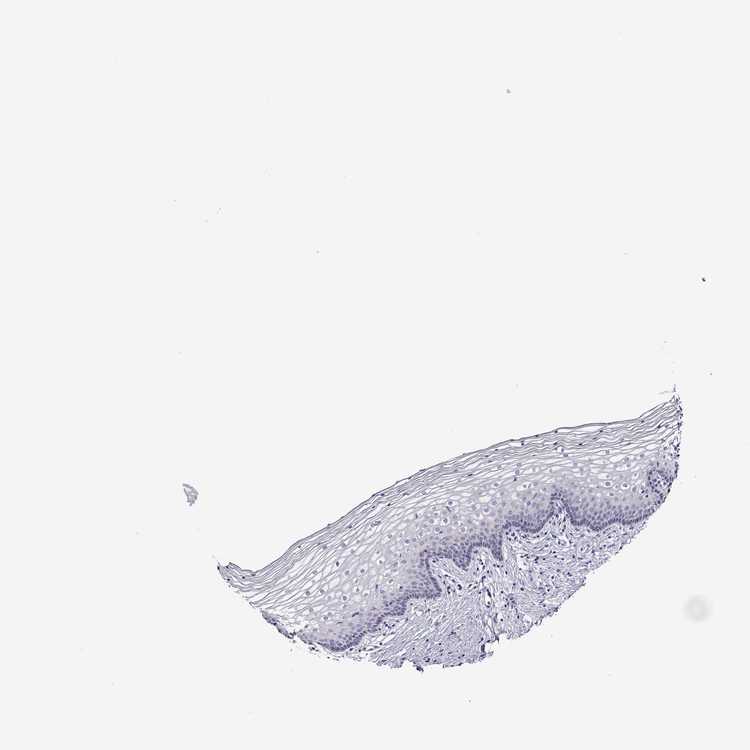

VAGINA - Antibody stainingi

Antibody staining in the annotated cell types in the current human tissue is reported as not detected, low, medium, or high, based on conventional immunohistochemistry profiling in selected tissues. This score is based on the combination of the staining intensity and fraction of stained cells.

Each image is clickable and will lead to virtual microscopy that enables deeper exploration of all samples and also displays staining intensity scores, fraction scores and subcellular localization as well as patient and tissue information for each sample.

Antibody HPA004469

Squamous epithelial cells Not detected